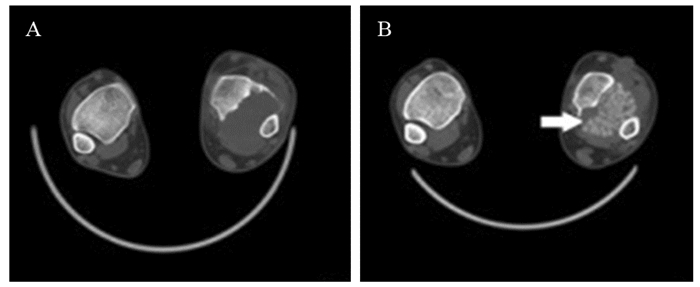

CampanacciⅠ级骨巨细胞瘤行单纯刮除术后均无复发;CampanacciⅡ级骨巨细胞瘤行单纯刮除术、扩大刮除术及瘤段或分块切除术后复发率分别为17.3%(23/133)、7.1%(7/98)、0(0/10);CampanacciⅢ级骨巨细胞瘤行单纯刮除术、扩大刮除术及瘤段或分块切除术后复发率分别为28.1%(18/64)、6.9%(6/87)、4.5%(2/44),见图 1~3。两两比较三种手术后复发率的差异,结果显示Ⅲ级骨巨细胞瘤单纯刮除术后复发率明显高于扩大刮除术(P < 0.001)以及瘤段或分块切除术(P=0.002),差异有统计学意义,而扩大刮除术与瘤段或分块切除术后复发率差异无统计学意义(P=0.885);Ⅱ级骨巨细胞瘤三种手术后复发率的差异无统计学意义(P > 0.017),见表 3。

![]() 图 2 骨巨细胞瘤单纯刮除术后复发病例CT结果Figure 2 CT scan of one recurrence case with giant cell tumor of bone after simple excochleationA 24-year-old male with giant cell tumor of bone in the left distal tibia suffered tumor recurrence 3 months after anterior approach surgery with simple excochleation and inactivation of bone graft because of exposure difficulty in the internal posterior side and insufficient scraping range; A: before operation; B: 3 months after surgery

图 2 骨巨细胞瘤单纯刮除术后复发病例CT结果Figure 2 CT scan of one recurrence case with giant cell tumor of bone after simple excochleationA 24-year-old male with giant cell tumor of bone in the left distal tibia suffered tumor recurrence 3 months after anterior approach surgery with simple excochleation and inactivation of bone graft because of exposure difficulty in the internal posterior side and insufficient scraping range; A: before operation; B: 3 months after surgery![]() 图 3 骨巨细胞瘤大块切除术后病例影像学检查结果Figure 3 Imaging results of one case with giant cell tumor of bone after block resectionA 26-year-old female with giant cell tumor of bone in the 1st sacrum found no evidence of recurrence 53 months after surgery with the whole block below the 3rd sacrum resected and nerve-retained enlarged excochleation above the 3rd sacrum. A, B: preoperative CT scan; C: preoperative MRI; D: X-ray 53 months after surgery; E: CT scan 53 months after surgery表 3 手术方式与骨巨细胞瘤复发率的关系Table 3 Relationship between operation method and recurrence rate of giant cell tumor of bone